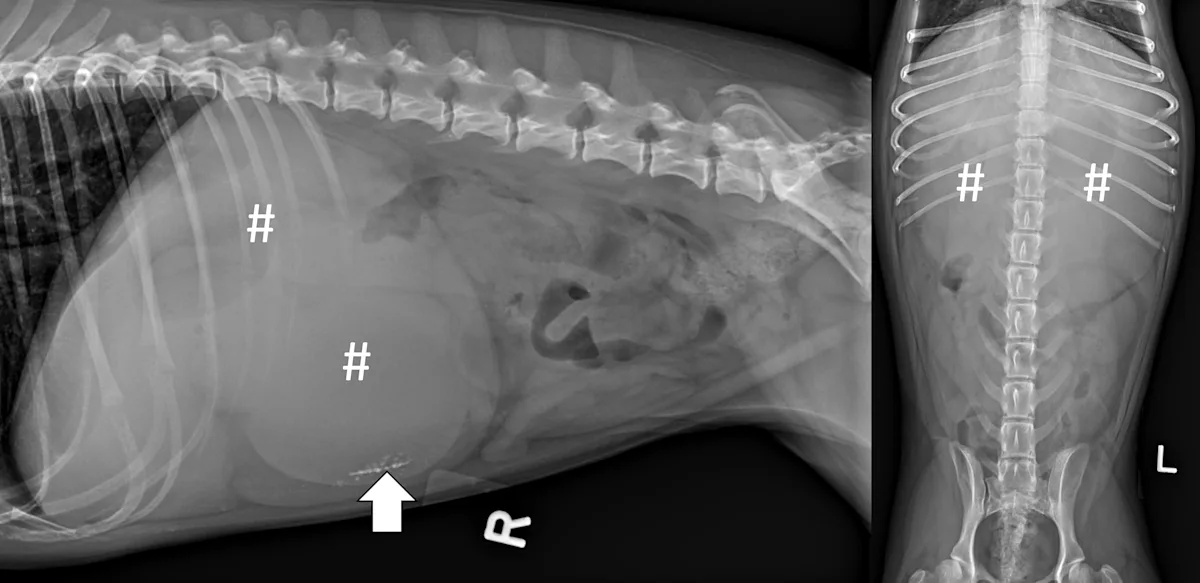

A complete radiographic study includes left lateral, ventrodorsal, and right lateral projections. Obtaining a left lateral projection and performing projections in the aforementioned order can improve visualization of the pylorus and duodenum by shifting gas into the lumens.3 Normal intraluminal gas is an in vivo negative contrast agent that can make soft tissue opaque foreign bodies (eg, cloth) easier to see (Figure 1).

Three-view abdominal radiographs of a 6-year-old spayed dachshund with an acute pyloric outflow obstruction secondary to a surgically confirmed foreign body (cloth). The stomach (pound signs) is moderately dilated with gas and fluid. On the left lateral and ventrodorsal projections, gas outlines an irregularly shaped soft tissue opaque foreign body (arrows) within the pylorus that extends into the duodenum. On the right lateral projection, the foreign body is more difficult to see because it is surrounded by similarly opaque gastric fluid.